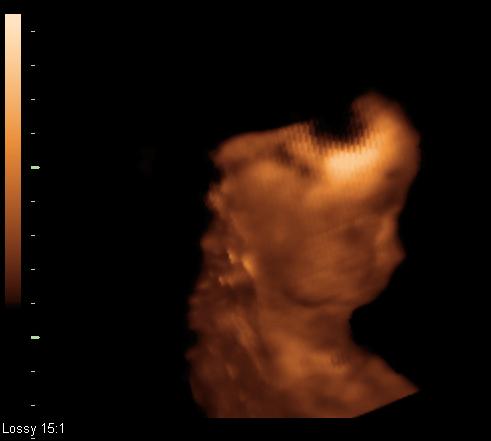

Fogalmunk se volt, hogy van köve, eddig semmilyen panasza nem volt.

Most a kivizsgálás során kiderült, hogy van egy kicsi és egy nagyobb kő. A kicsi indult el, ez okozta most a galibát, de szerencsére kijött.

A nagy még bent van a vesében, azt lehet, hogy robbantani fogják. (De ez sem egyszerű, mert van valami kis szűkölet is, és ha szétrobbantják, nem biztos, hogy ki tudnak jönni a darabok. Szóval lehet, hogy jobb, ha nem bántják, amíg nem okoz problémát...) Ja, azt nem is írtam, hogy 1 hónap múlva kell kontrollra mennie, hogy mi legyen ezzel a kővel.... az már tényleg érdekes lesz, ha akkor lesz valami beavatkozás